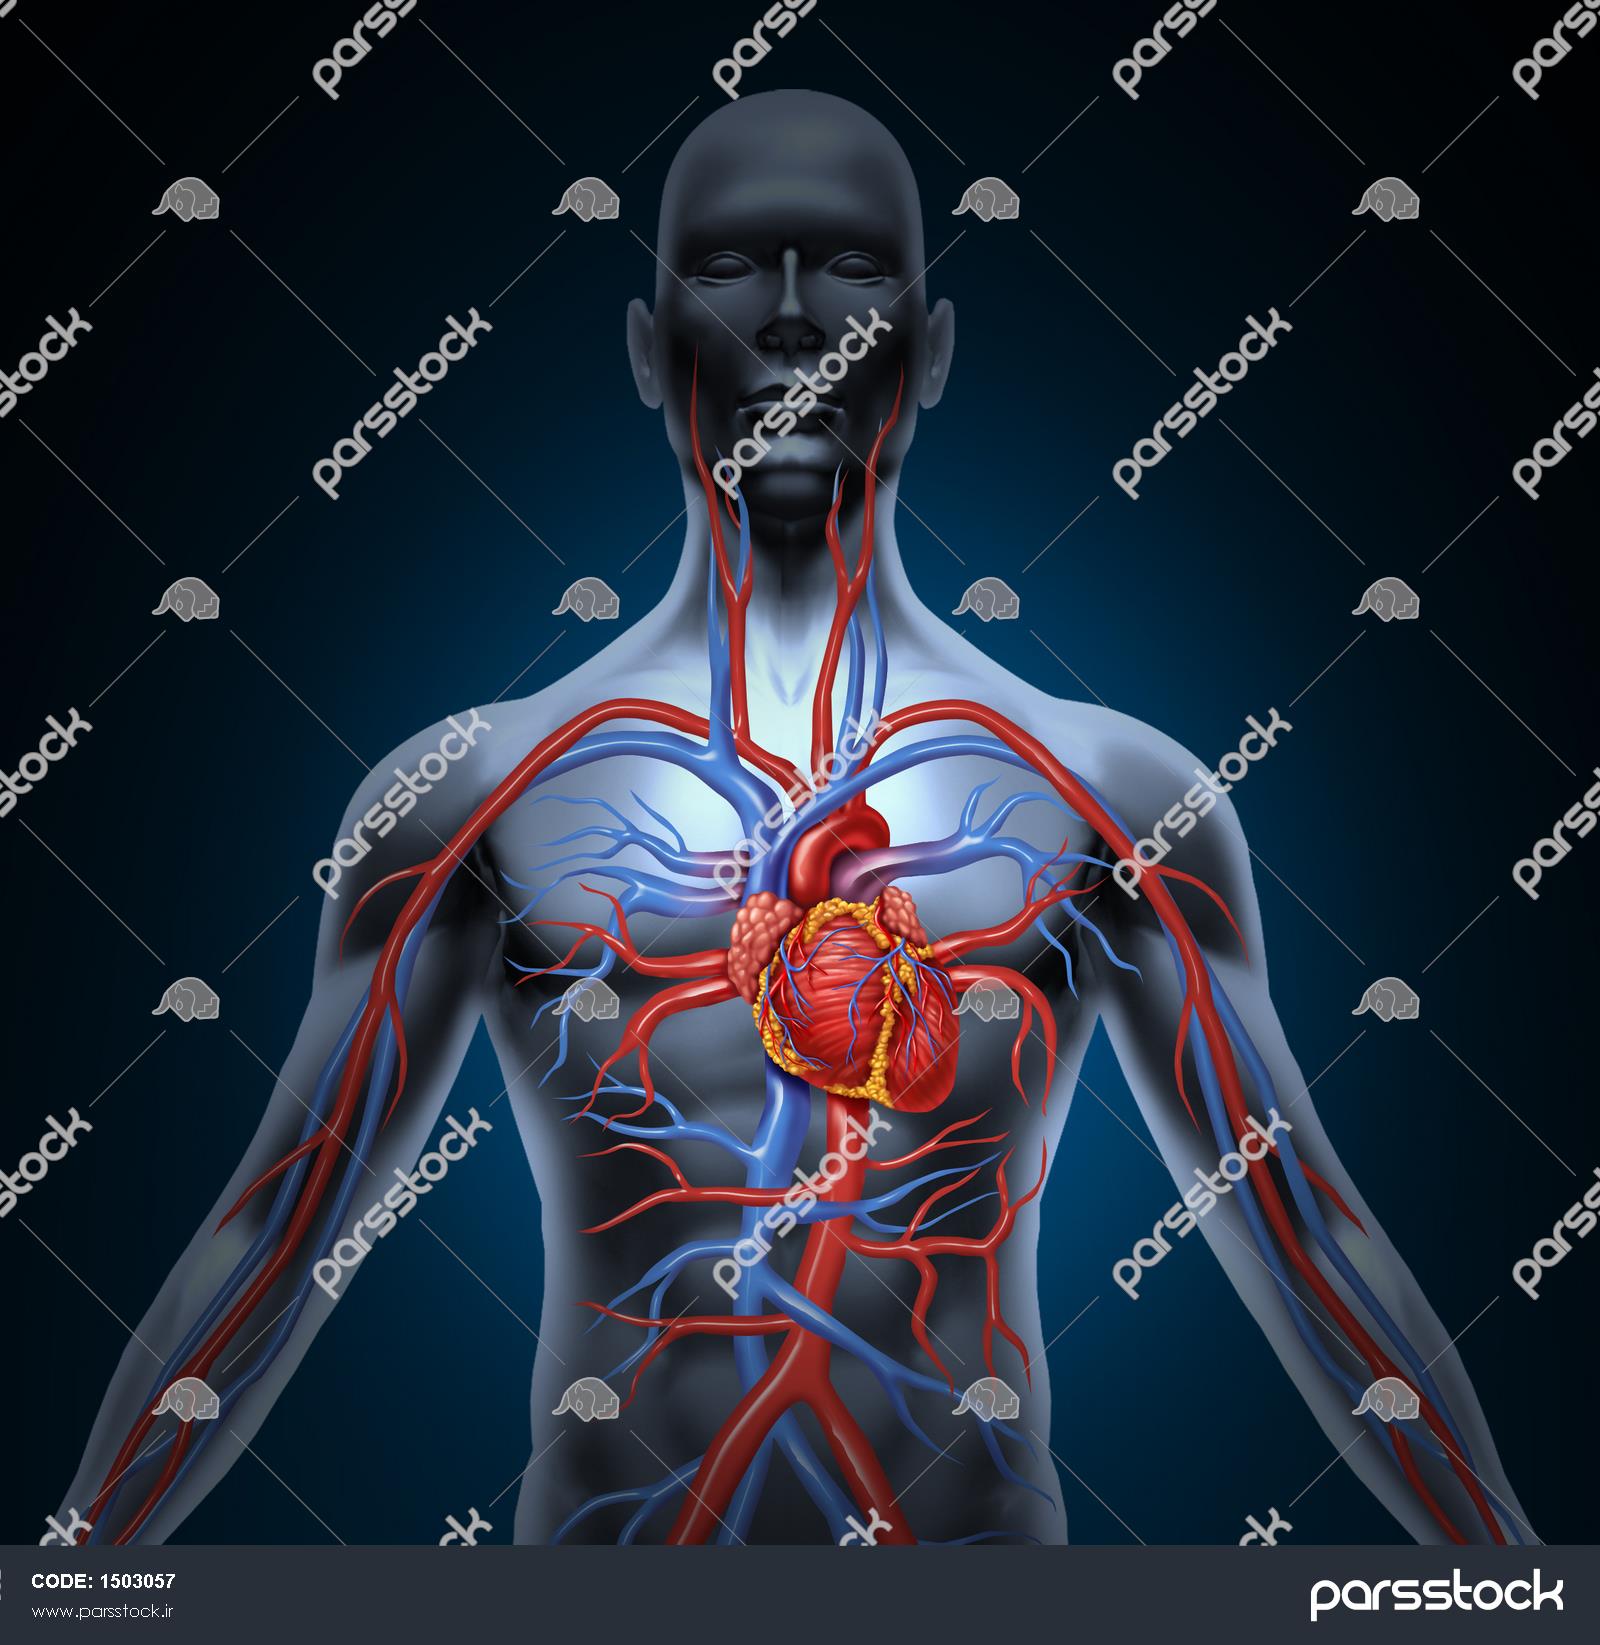

عکس اسکلت بدن انسان با کیفیت. عکس اسکلت عکس اسکلت برای پروفایل عکس اسکلت انسان عکس اسکلت خفن عکس اسکلت بدن انسان با کیفیت عکس اسکلت بدن انسان عکس اسکلت ترسناک عکس اسکلت فانتزی عکس اسکلت فانتزی دخترانه پرچم عکس اسکلت. عکس با کیفیت اسکلت داخلی انسان و درد و گرفتگی در ناحیه استخوان زانو ویژه استفاده در امور تبلیغاتی و تجاری طراحی کاتالوگ بروشور و تراکت با موضوع پزشکی فیزیوتراپی ارتوپد دکتر روماتیسم فیریوتراپ طب فیزیکی. عکس اسکلت بدن انسان زن و مرد آناتومی ساتین 16 سپتامبر 2017. اسکلت داربست بدن است تمام قسمت های بدن روی اسکلت قرارگرفته اند بدن انسان از ۲۰۶ قطعه استخوان تشکیل شده است این استخوان ها طوری با نظم کنار هم قرار گرفته اند که انسان را قادر می سازد حرکات دقیقی داشته باشد.

اسکلت جمجمه و گردن انسان ستون فقرات آناتومی اسکلت جمجمه و گردن انسان ستون فقرات آناتومی تصویر با کیفیت را از لینک زیر می توانید دانلود کنید. ۱ مطلب با کلمه ی کلیدی عکس اسکلت بدن انسان با کیفیت ثبت شده است گالری نسیم جدید ترین و با کیفیت ترین عکس های مناسبتی. عکس با کیفیت آناتومی اسکلت بدن انسان و درد و دیسک در قسمت مهره های ستون فقرات کمر ویژه استفاده در امور تبلیغاتی و تجاری طراحی کاتالوگ بروشور و تراکت با موضوع بیمارستان ها و کلینیک ها و درمانگاه ها و مطب ها پزشکان و.